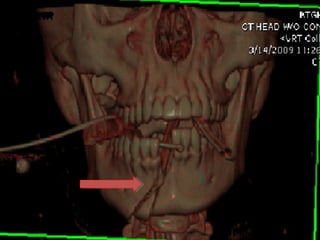

• #54 Mandible fracture